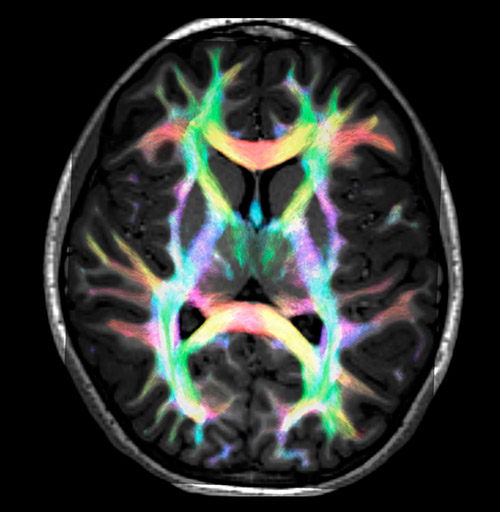

All images were created from the same acquisition in a child using Ingenia 3.0T CX and 32-channel dS Head coil. Diffusion data was acquired at b-values 0, 500, 1000, 2000, 3000. The use of high b-values (3000 s/mm2) effectively suppresses extra-axonal water signal and provides high angular resolution.

DEC TDI: directionally encoded color track-density imaging

CSD of multishell DWI results in the white matter FOD at each voxel. Unlike the conventional diffusion tensor model, this approach enables accurate modeling of multiple fiber populations within a single voxel.

Crossings of the corpus callosum, corticospinal tracts, and the superior longitudinal fasciculus are shown.

Super-resolution directionally encoded color track-density imaging overlaid on T1-weighted structural MRI.